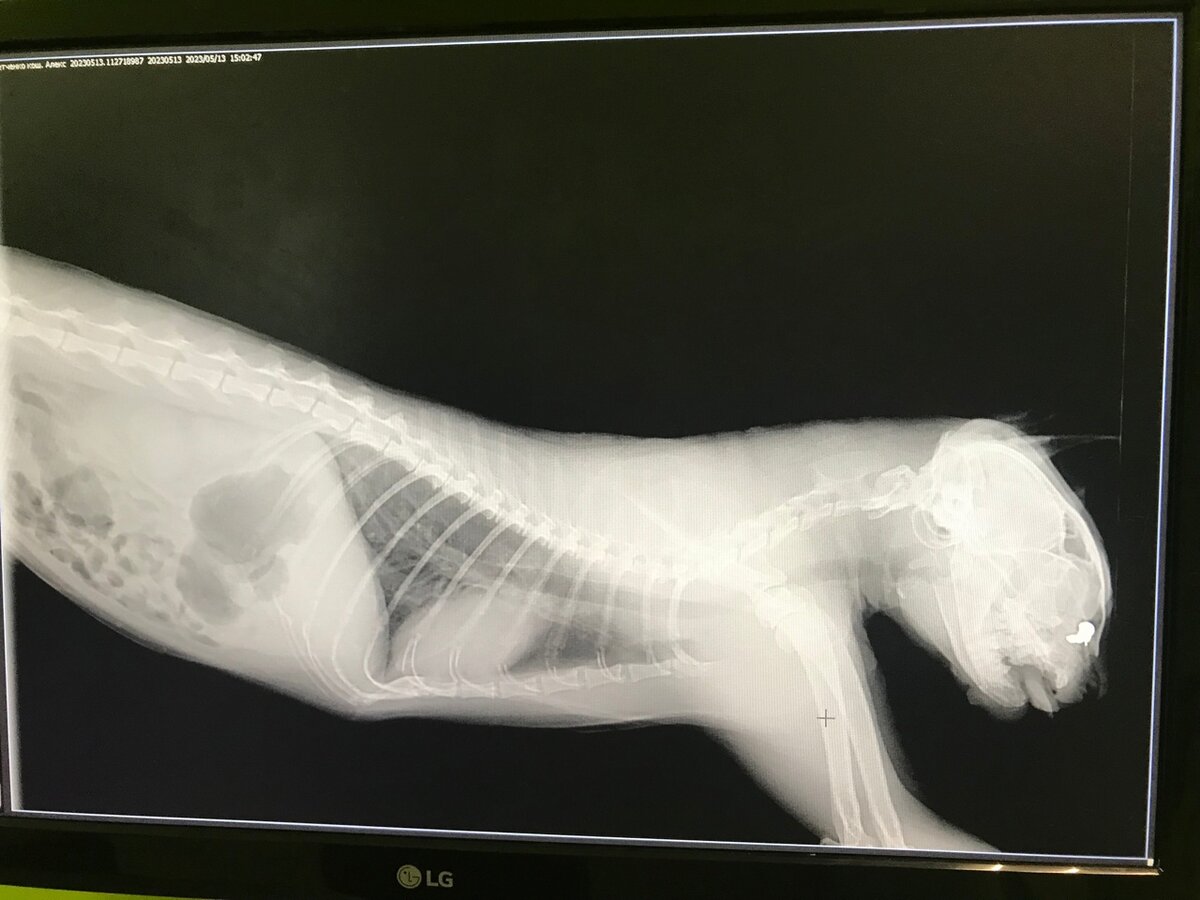

Абсцесс мы вылечили, привели котика в порядок. А недавно у него начались проблемы с зубами. В ходе лечения и выяснилось что у Павлуши иммунодефицит кошек. А еще у него в носу пуля! Представляете, кто-то стрелял по котику. Удалять пулю сейчас нельзя, да и в принципе она ему не мешает, ведь он с ней живет скорее всего много лет. Диагноз иммунодефицит у кошек звучит очень страшно, но последнее время мы поняли, что многие люди перестают бояться и все чаще берут домой таких особенных животных.